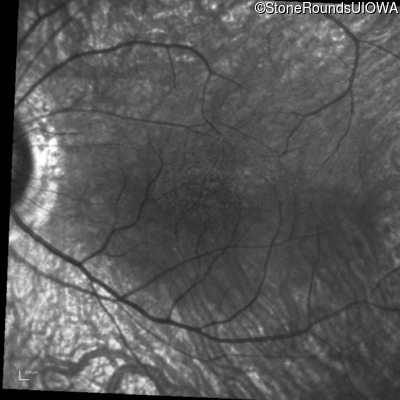

Infrared Fundus Photograph - Left - 20/50

Exemplar